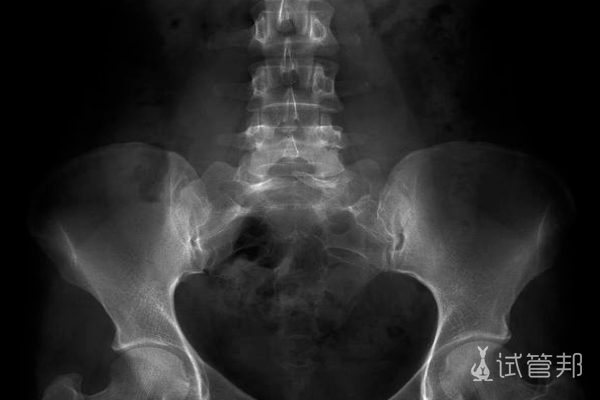

神经管畸形是胎儿神经系统发育过程中出现的结构异常。神经管在胚胎期形成,最终分化为脑和脊髓。如果此过程出现问题,可能导致以下几种类型的神经管畸形:

1.脑脊髓管闭合不全:神经管未完全闭合,导致脑和脊髓部分暴露,如脊柱裂和腦膜膨出。

3.其他神经管畸形:包括无脑畸形和先天性脊柱侧弯等较少见的类型。